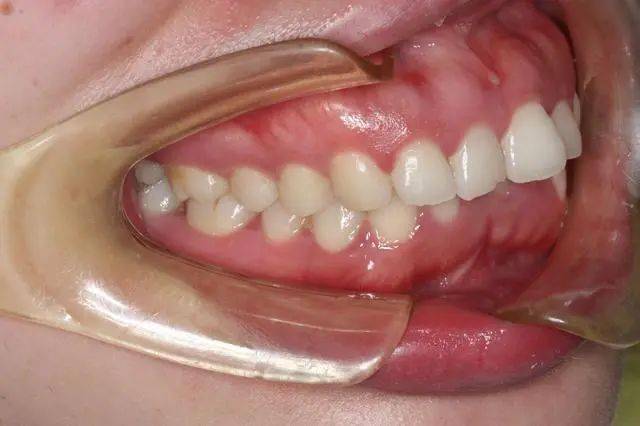

前牙反颌的临床表现及治疗原则 前牙反颌为常见的错颌畸形,可出现在乳牙期、替牙期和恒牙期,主要是下切牙位于上切牙的唇侧,形成不同程度的反覆颌和反覆盖,是由于多种原因引起的,有牙源性、功能性和骨... 牙齿矫正 令狐逸 1436 2024-03-14

前牙反颌的分类是什么 正中咬合时,前牙的反覆颌、反覆盖关系称为前牙反颌,俗称“地包天”。它是牙颌畸形的另一种常见的类型,发病率高。如果不及时矫治,就会对患儿面部前后向的正常发育产生严... 牙齿矫正 南光耀 952 2024-02-26

前牙反颌有哪些临床表现 正中咬颌时,前牙的反覆颌、反覆盖关系,称为前牙反颌,俗称“地包天”。前牙反颌显而易见,也有特定的面形,如面中1/3凹陷,或下颌明显前突等。... 牙齿矫正 厉涵山 699 2023-12-28